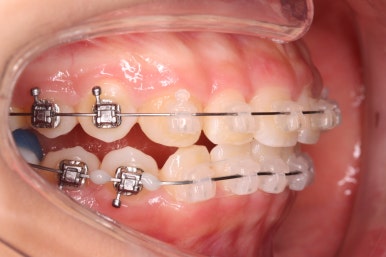

예상한대로 자리만 충분히 마련해주니 그동안 나오지 못하고 막혀있던 치아가 슬그머니 고개를 내밀고 있습니다.

좀 더 기다렸다가 좀 더 올라오면 장치를 부착해서 정리해주기만 하면 되겠습니다.

부산치아교정잘하는곳 키다리아저씨치과에서는 치아가 올라오자마자 장치를 부착하여 가지런하게 해줍니다. 이제 어느 정도 큰 그림은 그려졌다고 보시면 되겠습니다.

치아가 잘 올라온 것을 볼 수 있습니다.